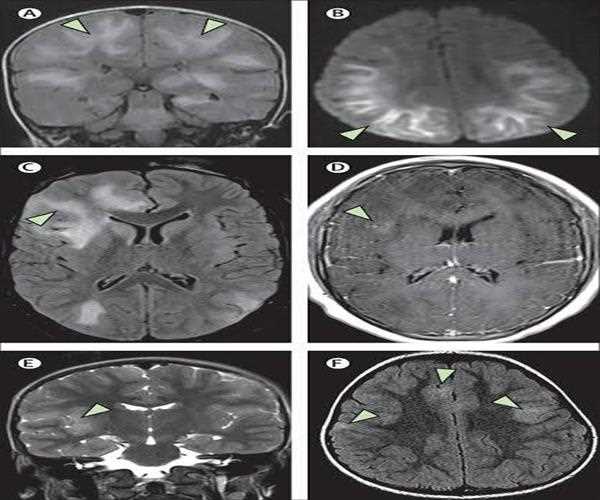

• MRI results showed that patients who recovered from COVID-19 had significantly higher susceptibility.

• This was in regards to values in the frontal lobe and brain stem compared to healthy controls.

• The clusters obtained in the frontal lobe primarily show differences in the white matter.

The heart, lungs, or other organs may change as a result of COVID-19, according to research, even in asymptomatic patients. The most recent study examined the effects of COVID-19 on the brain using susceptibility-weighted imaging, which is being presented at the annual meeting of the Radiological Society of North America (RSNA).

Mishra said in a release that 'our work exposes this novel element of the neurological impacts of COVID-19 and shows severe abnormalities in COVID survivors.' 46 COVID-recovered patients and 30 healthy controls' susceptibility-weighted imaging data were analysed by the researchers. Within six months of my recovery, imaging was done.